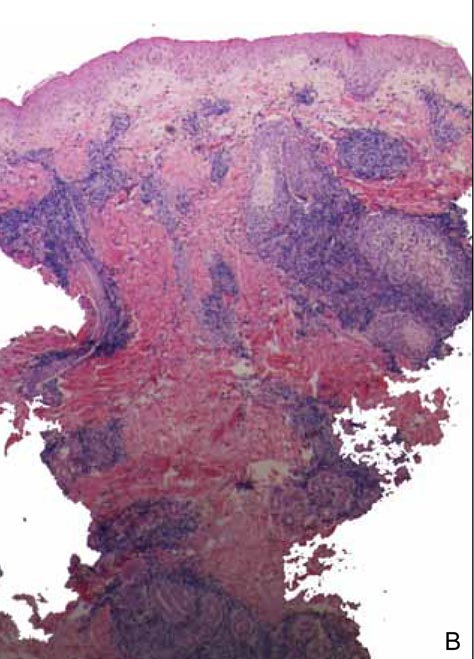

The characteristic histologic picture of LAFM in patch or plaque stage shows mucin deposition within hair follicles, similar to idiopathic FM. On histology, both conditions demonstrate dense lymphoid infiltrates around and within hair follicles as well as in the dermis (Figure). Most cases of LAFM show epidermotropism of lymphocytes between follicles, but this finding is not present in every case and often disappears when the disease advances to the tumor stage.1,19 Although Pautrier microabscesses (collections of lymphocytes within the superficial epidermis) are considered to be somewhat specific to MF, they are only present in a minority of cases.20 In a study by the International Society for Cutaneous Lymphomas,21 the only histopathologic criteria that showed any appreciable sensitivity or specificity in the diagnosis of MF were the presence of lymphoid cells with variable nuclear and cytoplasmic features and/or strikingly irregular nuclear contours with the presence of lymphocytes larger than those usually seen in inflammatory dermatoses. Despite these criteria, the study reported a high misclassification rate. A complicated scoring system for diagnosis of MF in patch- or early plaque-stage disease was proposed by the International Society for Cutaneous Lymphomas,21 which integrates clinical, histopathologic, molecular, and immunophenotypic criteria. However, these criteria have been continually debated in the literature and are only discussed in this article in relation to the association between MF and FM. Diagnosis of tumor-stage MF is not addressed in this article, as it is readily identified as lymphoma and is not easily confused with idiopathic FM.

Histopathology of 2 separate cases, both diagnosed as follicular mucinosis pending further follow-up. After close clinical follow-up, one case was diagnosed as mycosis fungoides (A) and the other as follicular mucinosis (B)(both H&E, original magnification ×2). Immunohistochemical stains were noncontributory, and T-cell gene rearrangement was positive only in the case of mycosis fungoides. Histopathology revealed mucin deposition in the hair follicles and a dense lymphoid infiltrate around and within the follicles in both cases. Pautrier microabscesses, cerebriform nuclei, and epidermotropism of lymphocytes between follicles were absent in the case of mycosis fungoides. |